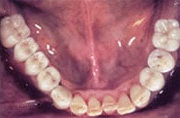

Heute

Ersatz der Unterkiefer-Seitenzähne beidseits mit natürlich aussehenden, festsitzenden Brücken und Kronen auf Implantaten.